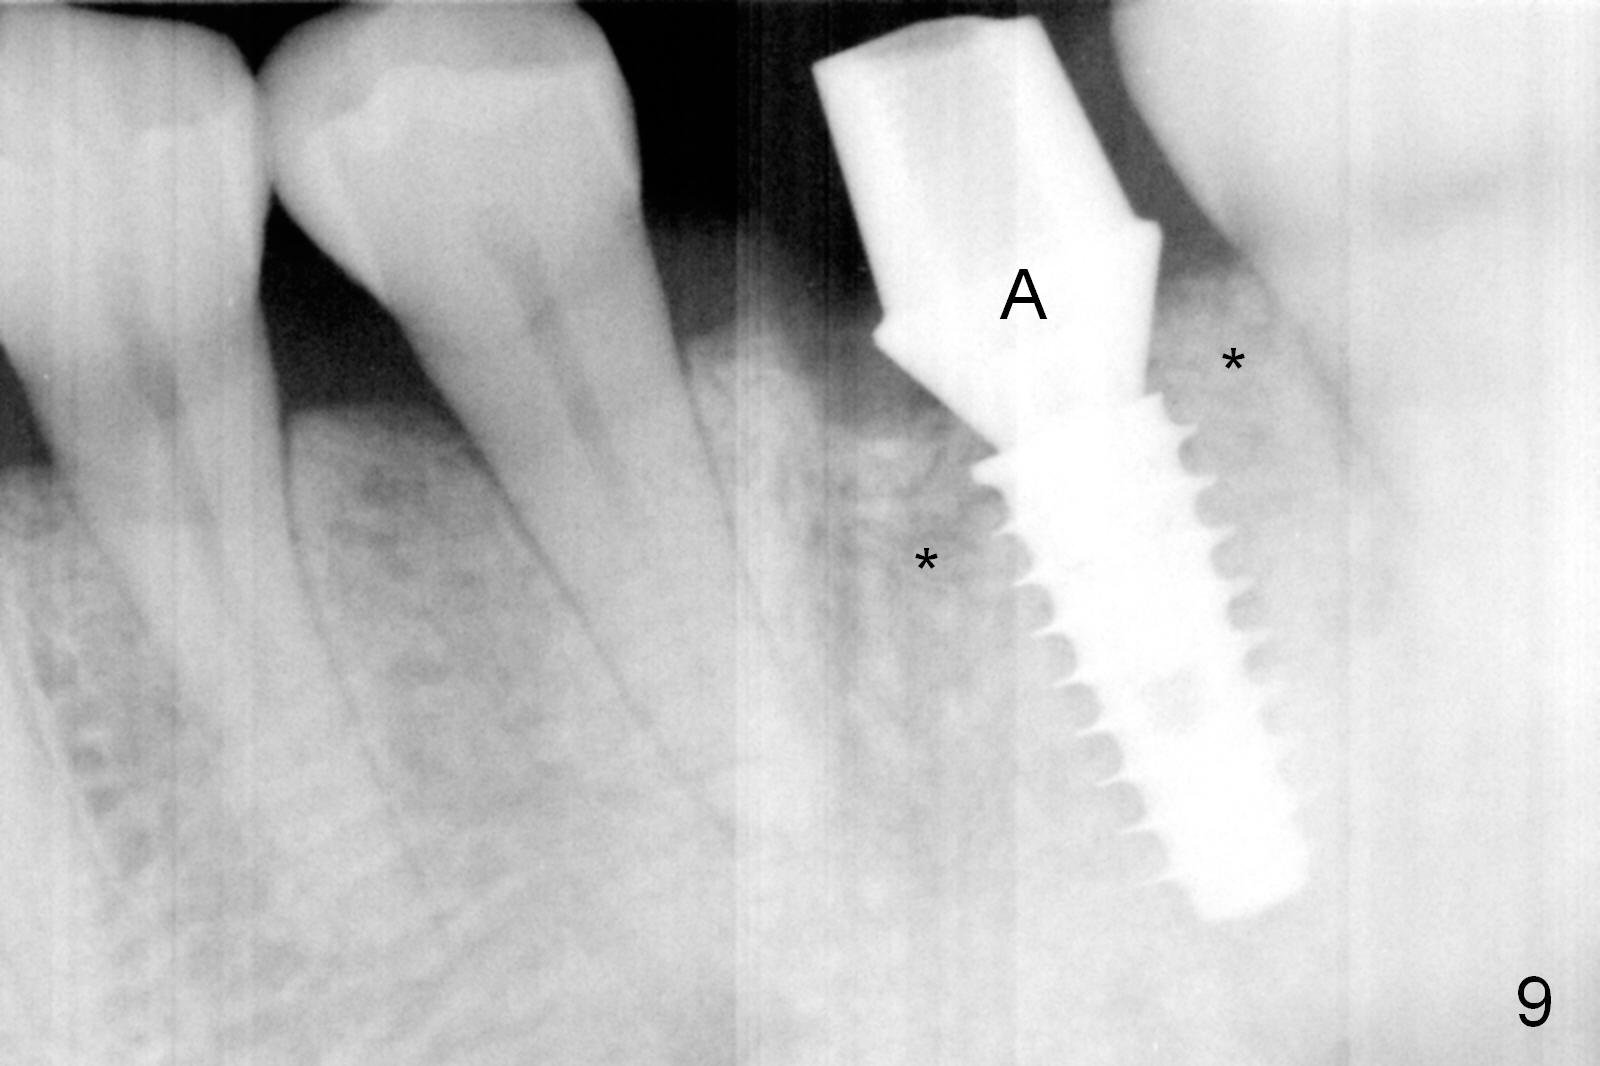

The asymptomatic tooth (#19) has a midbuccal fistula (Fig.1 <). The mesiobuccal pocket is 10 mm with purulent discharge from the sulcus (Fig.2,3). The mesiobuccal wall defect is confirmed when the tooth is extracted. Osteotomy is initiated lingually in the septum following septal crestoplasty (flattening) (Fig.4: using 1.6 mm drill for 9 mm). Since the lingual portion of the osteotomy is higher, it is difficult to use drill with stopper. For the narrow septum osteotomy, multiple drills are used sequentially (Fig.5 after 4.3 mm drill). A 4.5x11 mm dummy implant is placed (Fig.6) apparently too deep. When a 5x11 mm IBS implant is being placed, the depth is tightly controlled (Fig.7). The implant is apical to the lingual crest, whereas there is ~ 2 mm implant exposure buccally. That is, there is a large gap mesiobuccally (Fig.8), which is filled with .5-1.5 mm allograft (Fig.9 *). A 6.5x5.7(3) mm abutment (A) is placed and trimmed for an immediate provisional (Fig.10 P). The lacerated buccal gingiva is sutured as well as application of Perio Glue.